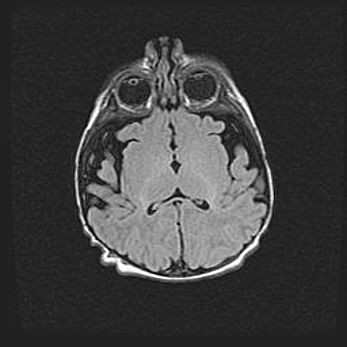

Лейкомаляция с кистозно-глиозной дегенерацией головного мозга.

Возраст: 2 месяца 25 дней

Вес: 6400 г

Окружность головы: 40 см

Срок гестации: 41 неделя

Лейкомаляцию относят к ишемически-гипоксическим повреждениям головного мозга, диагностируемым у новорожденных. При лейкомаляции в головном мозге обнаруживают очаги некроза, возникшие после тяжелой гипоксии и нарушения кровотока. В процессе морфогенеза очаги проходят три стадии: 1) развития некроза, 2) резорбции и 3) формирования глиозного рубца или кисты. Перивентрикулярная лейкомаляция (ПЛ) встречается примерно в 12% случаев среди новорожденных, обычно – у недоношенных детей, причем, частота ее зависит от массы, с которой младенец появился на свет. Наибольшее число малышей страдает лейкомаляцией, если масса при рождении 1500-2500 г.